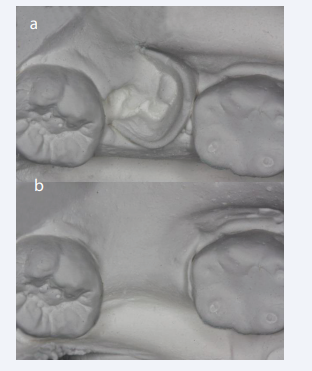

BPD diminished at 1 mm, 3 mm and 5 mm from the free gingival margin respectively of 5.91 ± 0.158 mm (p-value <0.01), 4.68 ± 0. 178 mm (p-value <0.001), and 3.75 ± 0.178 mm (p-value <0.001) (Figure 5a,b).

a,b: Occlusal view of the study casts at Time 0 (Baseline) and Time 3 (6  months) showing horizontal dimension tissue change.

Figure 5: a,b: Occlusal view of the study casts at Time 0 (Baseline) and Time 3 (6 months) showing horizontal dimension tissue change.